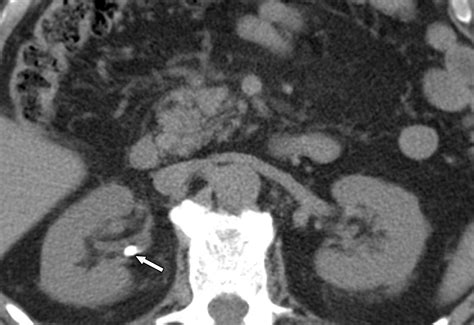

• Imaging Tests: CT scans and ultrasounds are commonly used to visualize the stones and assess their size and location.